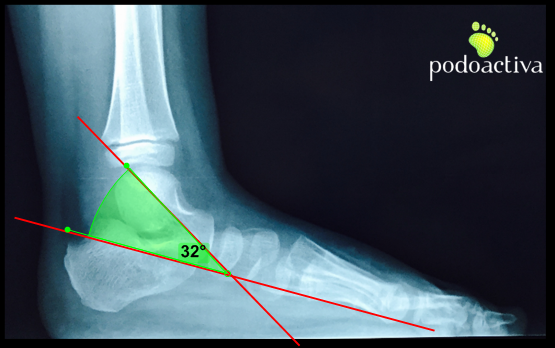

A nivel radiológico se pueden obtener medidas alteradas de diversos ángulos en proyecciones dorsoplantar y sagital. Prestaremos especial atención al ángulo radiográfico sagital TAMBA:

– El ángulo del eje del astrágalo con la base del primer metatarsiano (TAMBA):

– Entre 30º y 60º lo consideraremos astrágalo oblicuo.

– Valores por encima de 60º los consideraremos astrágalo vertical.